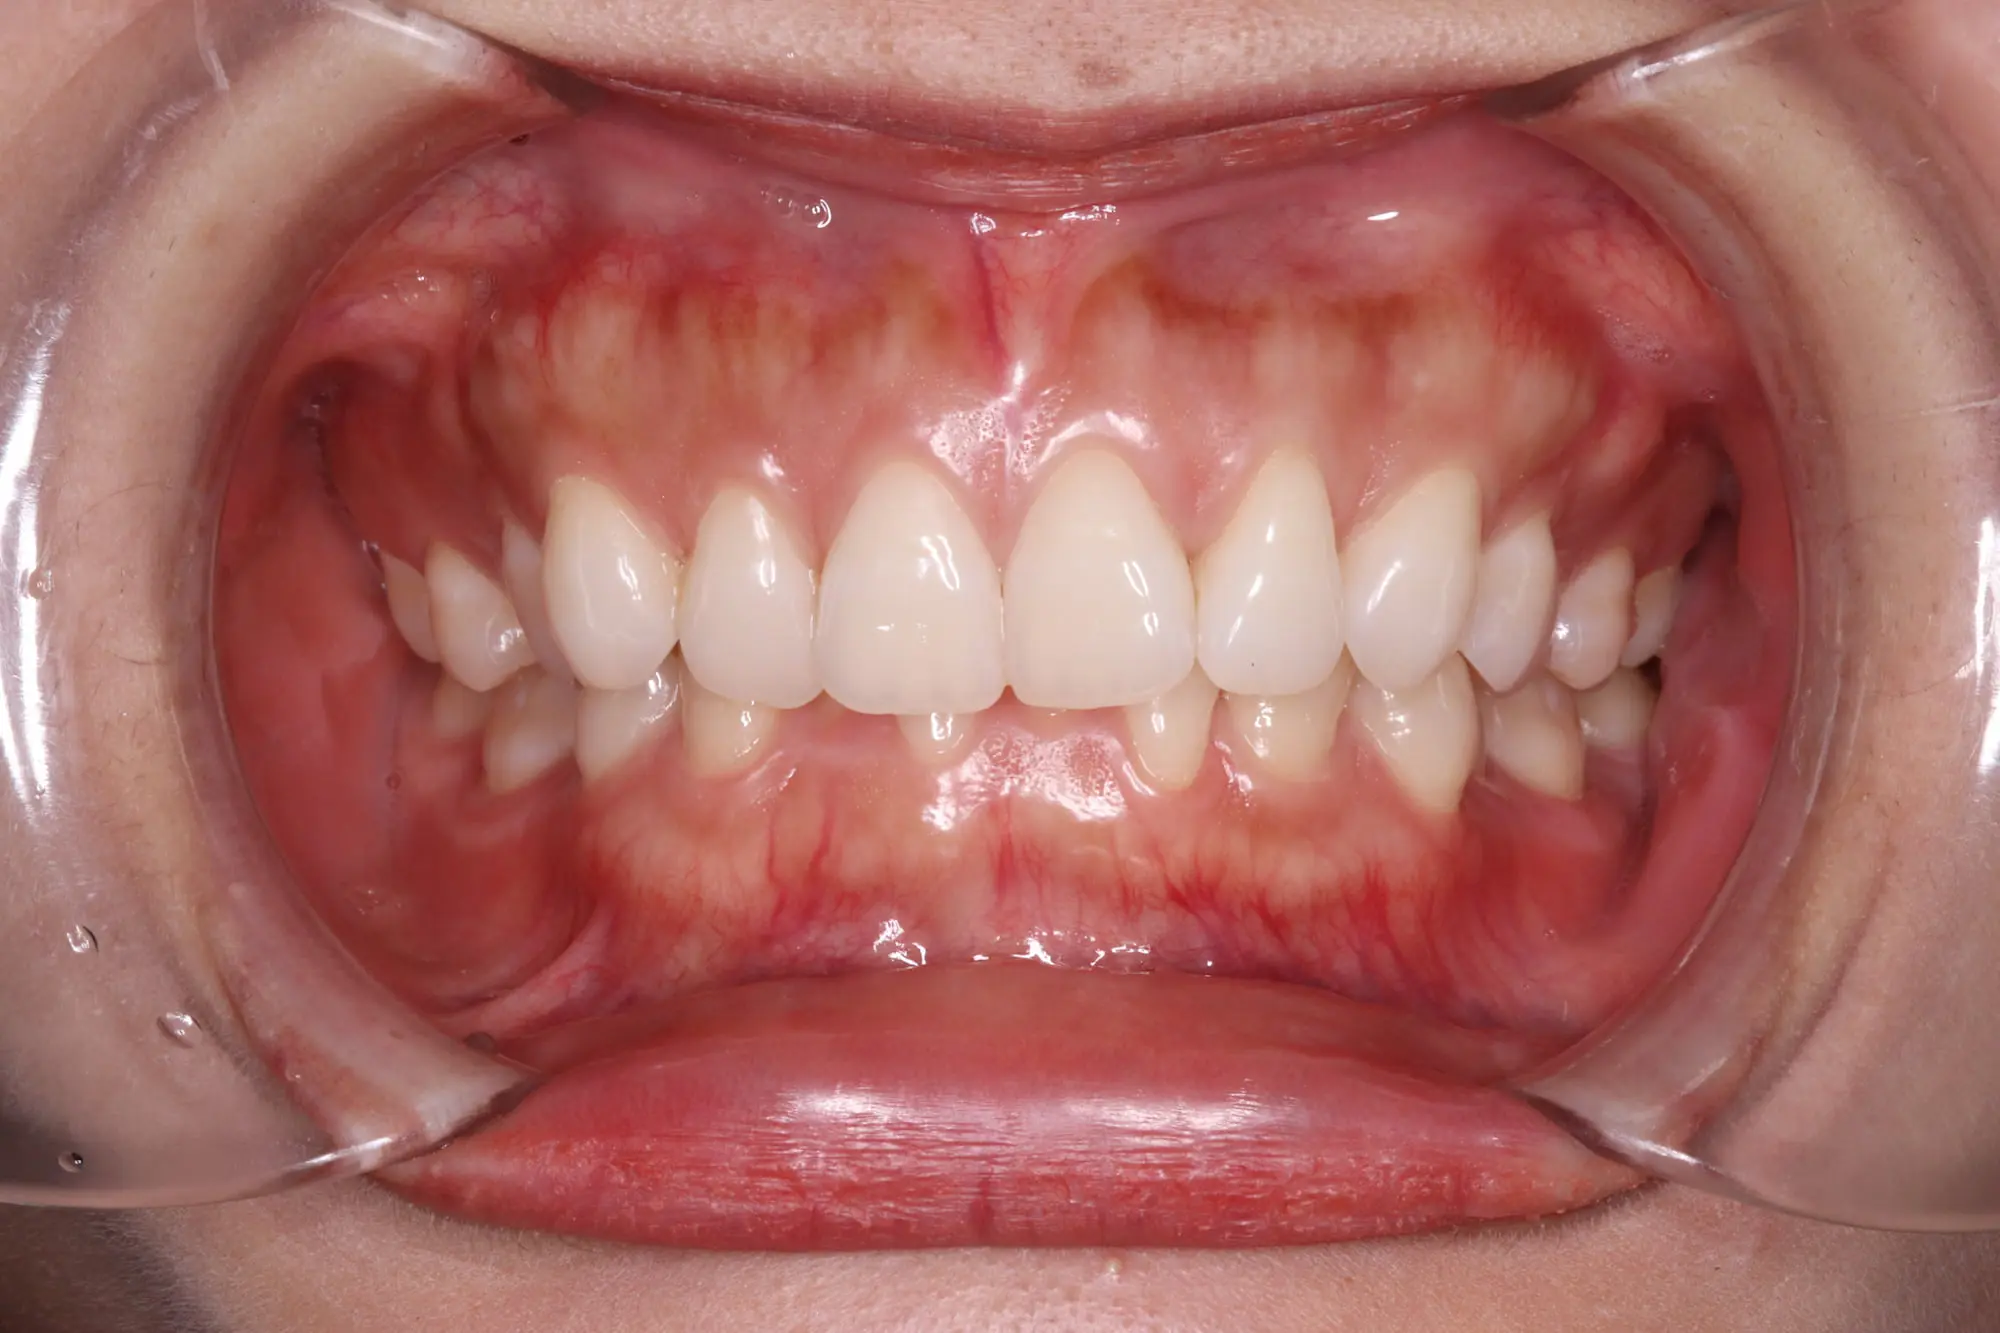

Crowding

Before